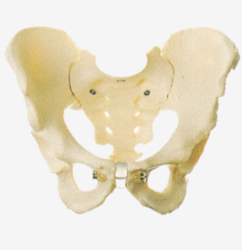

Skeleton Models(human bone, muscle, etc.)